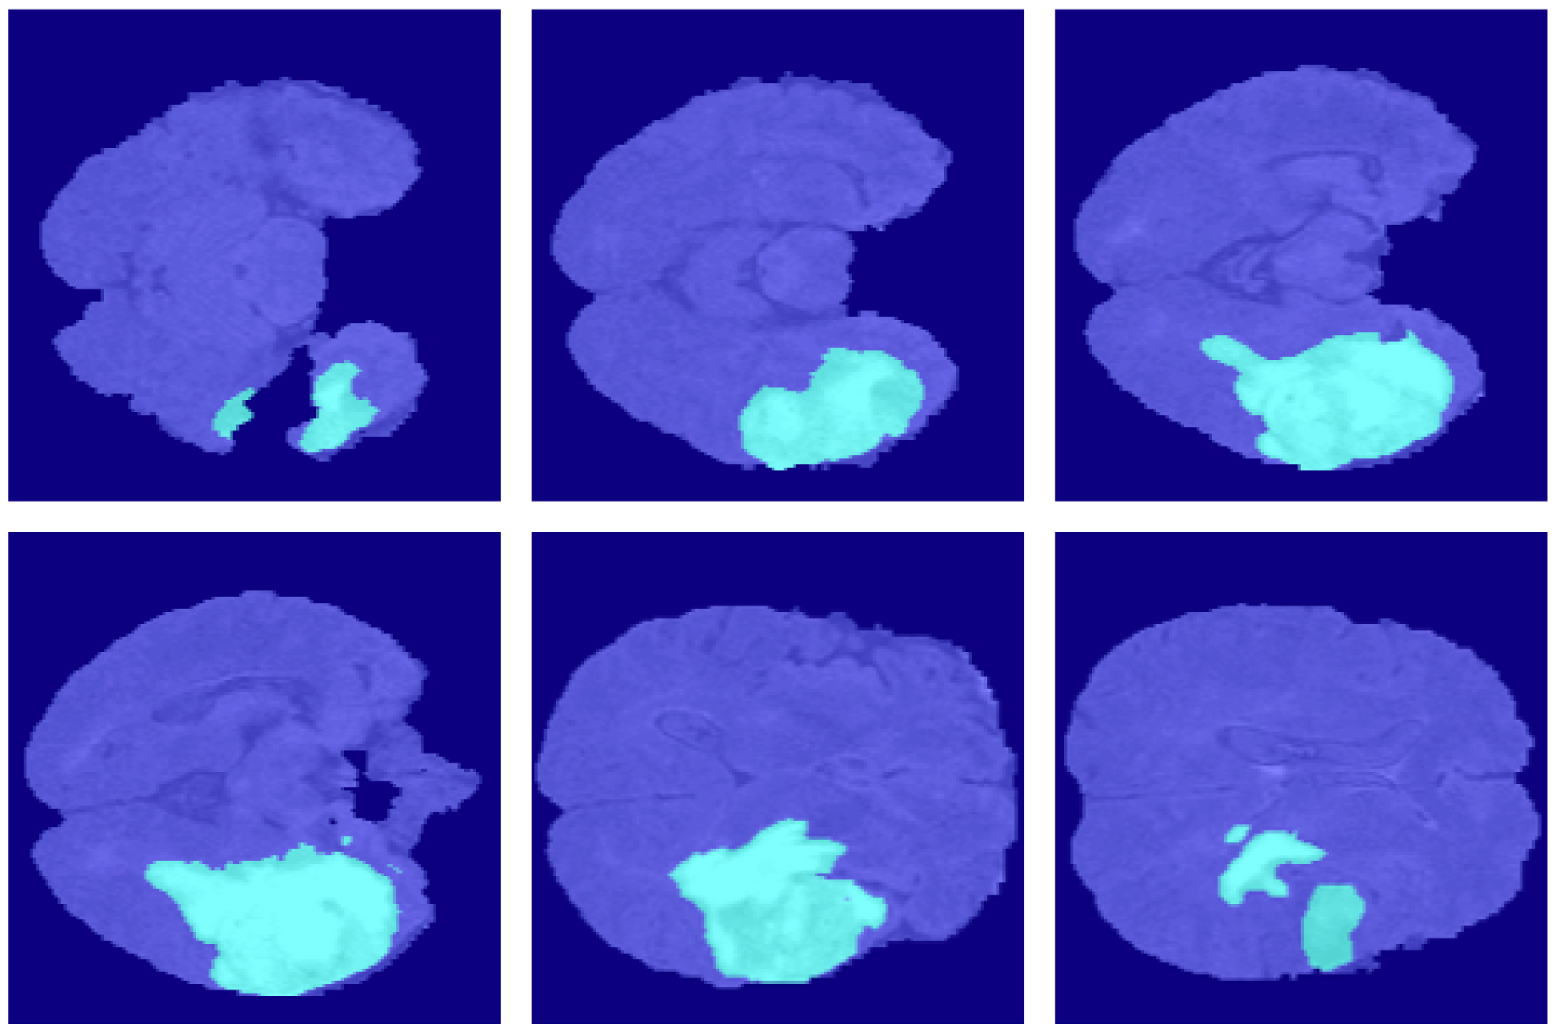

4.2. Segmentation Results

5. Discussion